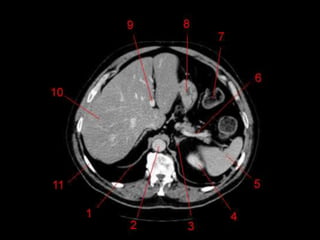

• TC: Tres fases

– Arterial (10 a 20 segundos)

– Fase venosa portal ( 30 segundos )

– Fase venosa hepática (60 segundos)

Técnicas de Imagem •US: Primeiro exame pedido ao: 1) dor no hipocondrio direito; 2) testes de função hepáticas anormais; 3) suspeita de malignidade. • TC: Tres fases – Arterial (10 a 20 segundos) – Fase venosa portal ( 30 segundos ) – Fase venosa hepática (60 segundos) • TC Portografia: Metastases.